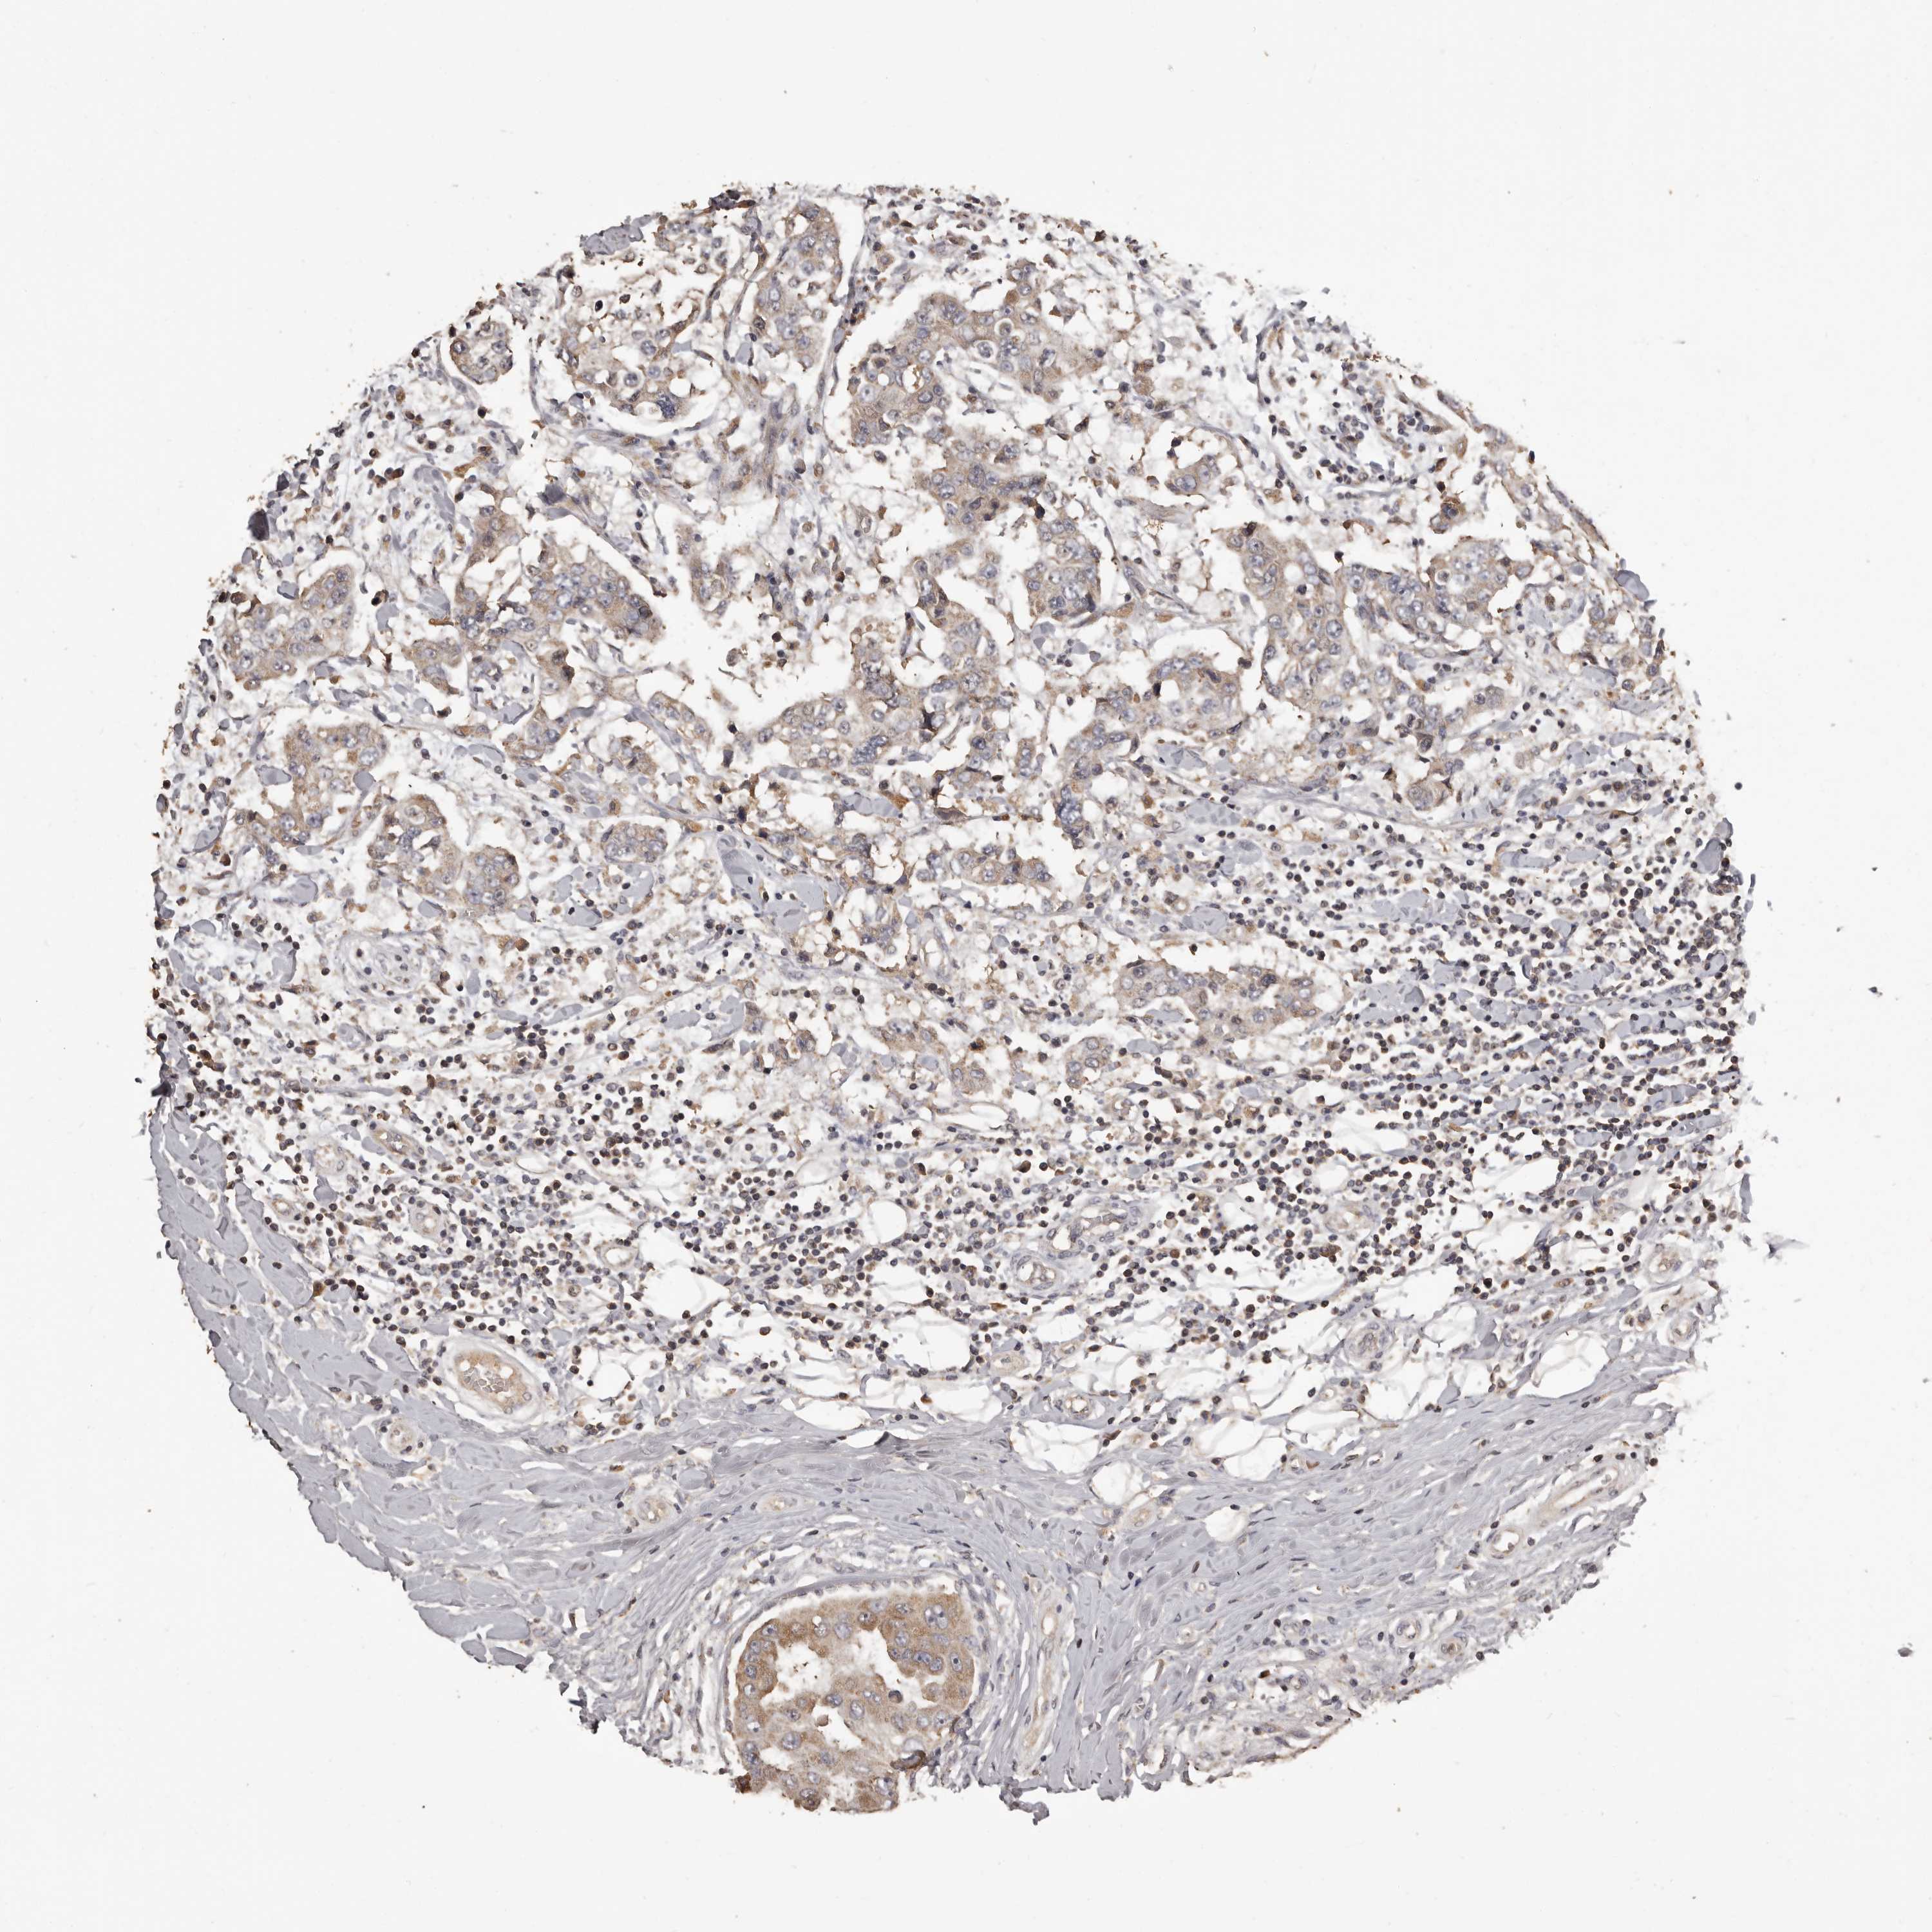

CANCER BREAST CANCER Show tissue menu

BRCA TCGA BRCA VALIDATION PROTEIN EXPRESSION

ANTIBODIES

AND

VALIDATION